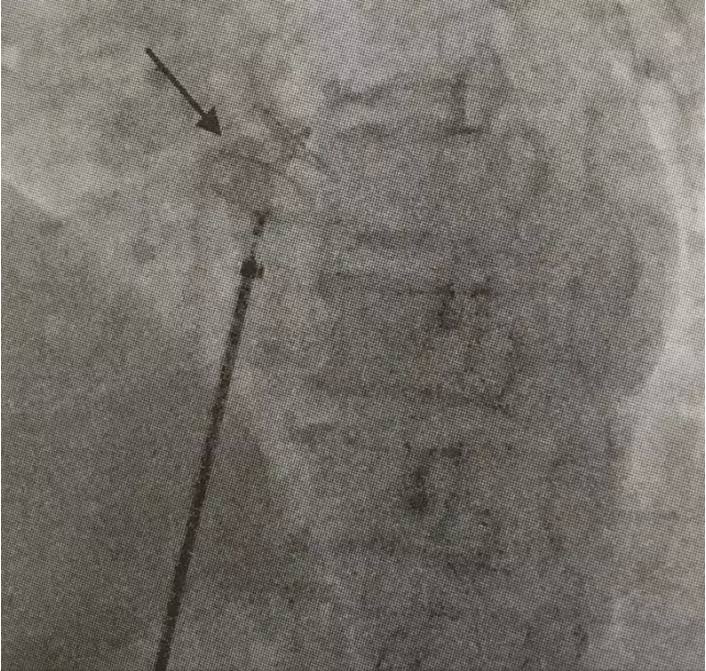

患者为中年女性,反复发生脑梗死,曾就诊于多家医院,考虑过多种临床诊断,包括:(1)患者为中年女性,有高血压病史,反复以脑血管系统受累症状就诊,但短期内既有前循环受累(见图1),又有后循环受累(见图2)的临床表现,且脑血管影像学评估包括超声以及脑血管造影均未见明显为异常。因此不支持脑血管本身病变所致。(2)低血糖症。在外院进行了延时OGTT试验,未发现明显低血糖,同时也进行了自身免疫性因素导致低血糖的筛查,无阳性发现,并且患者发作时表现为非经典低血糖症状(经典的Whipple)三联征:即低血糖症状、发作时血糖降低和供糖后症状迅速缓解),未补充糖症状也可以好转,排除了此种可能。(3)患者为女性,有系统性红斑狼疮家族史,为除外原发性或继发性抗磷脂综合征,入我院后查了LA-SCT(狼疮抗凝物)1.23升高,ANA 1:100,SSA阳性,虽然患者无明显系统受累表现,不能完全除外干燥综合征。但抗磷脂综合征需要3个月内复查抗磷脂抗体,阳性才能确诊。(4)除此之外,该患者临床发作特点为起病急骤、不同次发作累及脑血管不同部位、临床改善迅速,符合脑栓塞表现。但栓子来源于何处?缺血性脑血管病有20%来源于心源性栓塞。因此考虑有无心源性栓塞的可能。本患者虽有高血压病史,但并未发现有阵发或持续心房颤动。进一步于神经内科进行了TCD发泡试验,结果为阳性,提示存在心内秒或心外右向左分流。为进一步明确分流类型,又进行了经食管超声心动图检查及右心声学造影,结果提示存在卵圆孔未闭,且有右向左分流(左心房可见对比剂显影)(见图3)。因此考虑卵圆孔未闭引发的反常栓塞导致脑栓塞可能性最大。因脑栓塞反复发作,故进行了卵圆孔未闭封堵术(见图4)。术后服用阿司匹林100 mg Qd,氯吡格雷75 mg Qd,阿托伐他汀钙片10 mg Qd,随访半年未再发作脑栓塞症状。且复查狼疮抗凝物、抗磷脂抗体、β2-PGI均阴性,不考虑抗抗磷脂综合征,同时患者既往存在的平卧位低氧消失、劳力性低氧症状也消失(既往登山等活动时氧饱和度可降至92%,现一般登山活动无氧饱和度下降)。

图1. 患者第一次脑栓塞MRI示右侧小脑梗死(箭头所指)